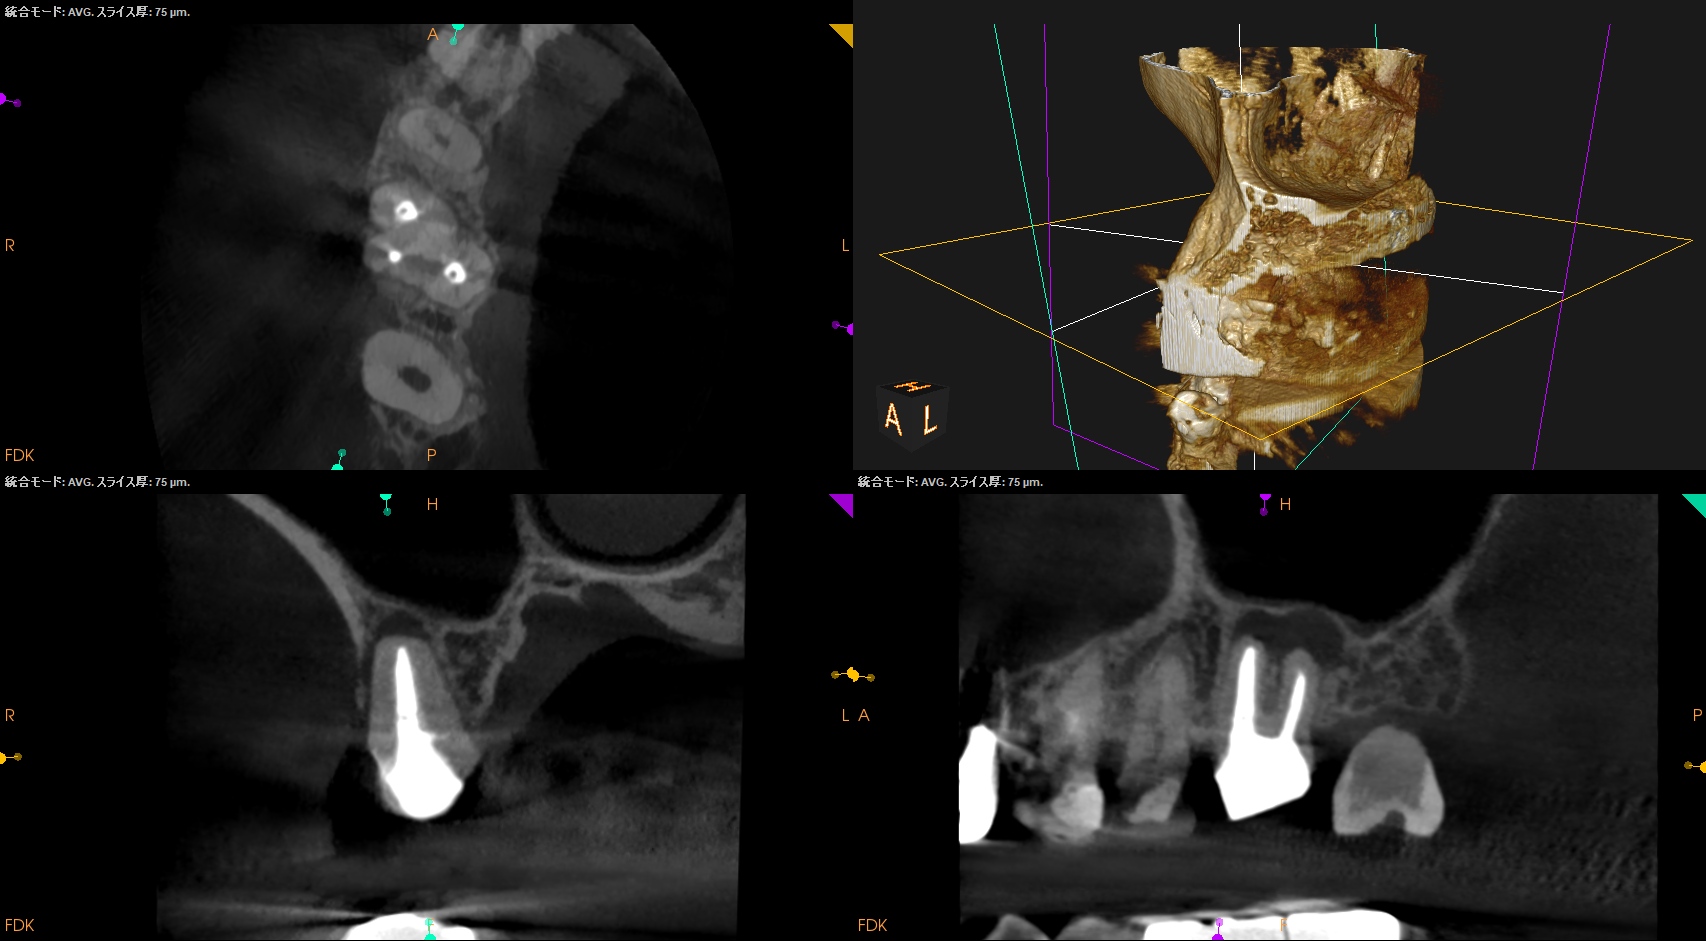

術後にPA, CBCTを撮影した。

#3

MB

DB

P

#14

#16